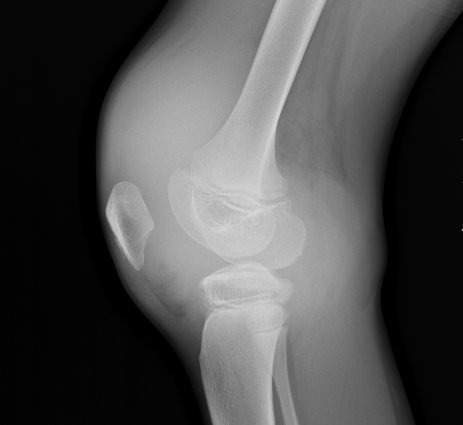

X-ray of young person with haemarthrosis - © Nevit Dilmen [CC BY-SA 3.0 or GFDL], from Wikimedia Commons